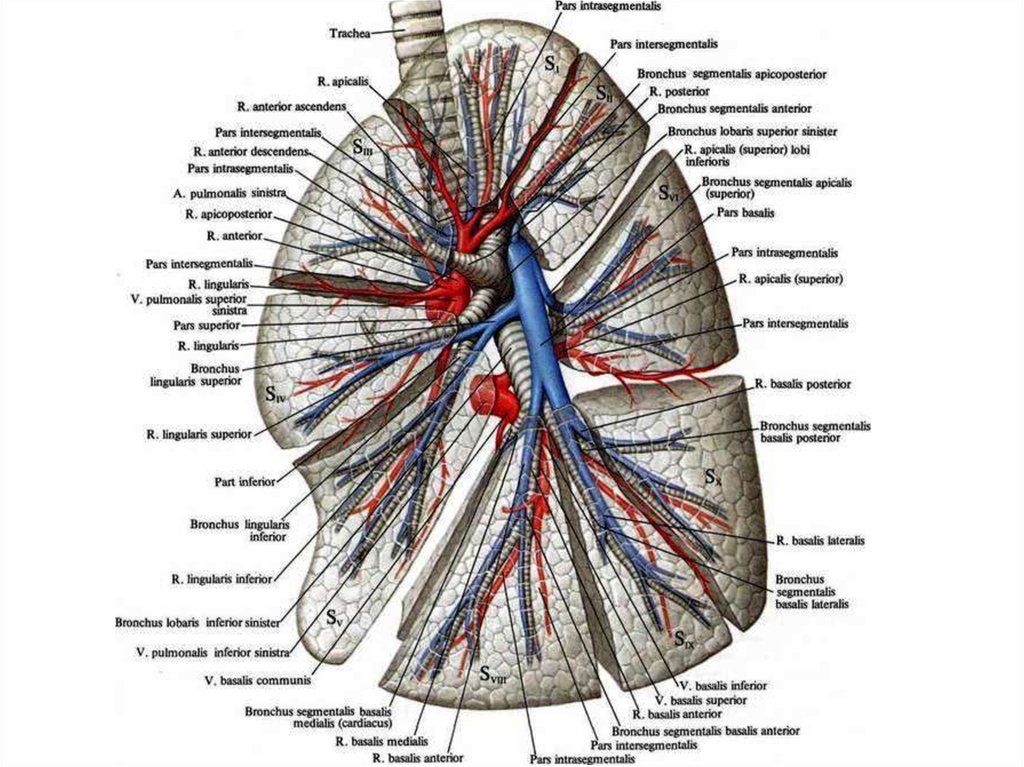

Анатомические изображения сегментов легких различных животных

Раздел: Другие животные